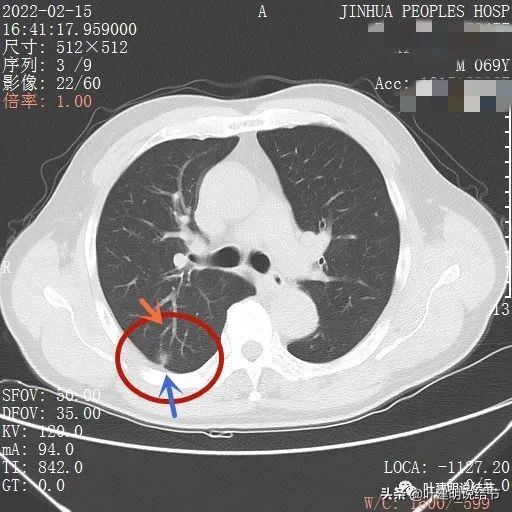

我们先来看下他的CT平扫5毫米层厚的图像:

病灶出现,有血管进入(桔色箭头),有轻微胸膜牵拉(蓝色箭头)

病灶基本实性,但边缘稍不平整,有的边比较平直,但仍是不光滑的